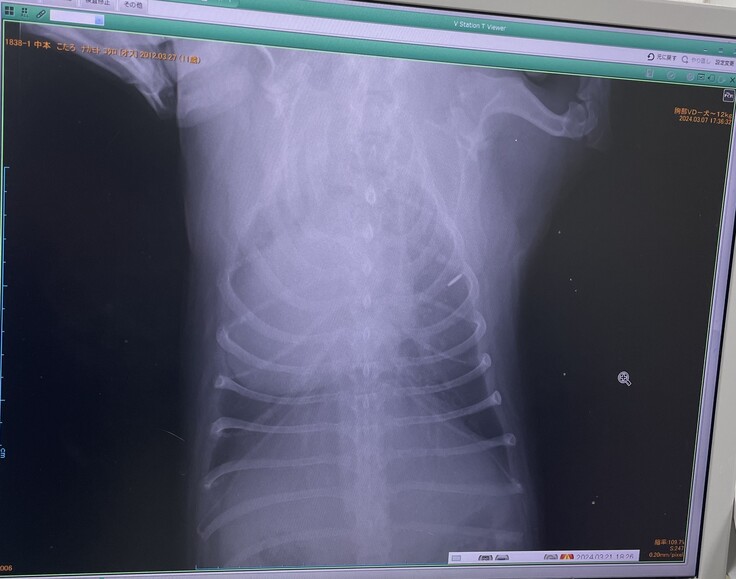

▼レントゲン

去年2月より心臓が大きくなっており肺・呼吸器が圧迫されていて咳が出る状態

(普通のわんこは真ん中に心臓があるが、こたろは左に寄っていて、

これが生まれつきなのかはわからないとの事)

※掲載画像はすべて病院からの許可をいただいています

■4月20日(土)診断結果■

二次診療施設での検査内容

かかりつけの病院とほぼ同じ検査・結果となりました。